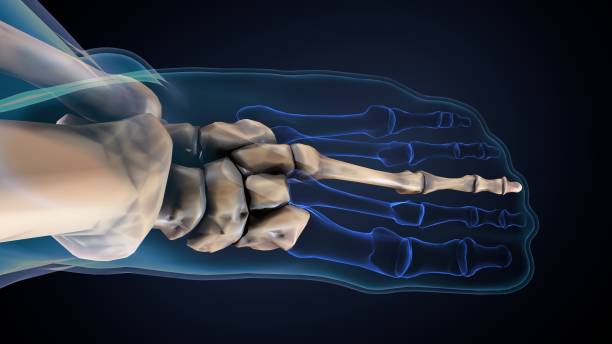

발뒤꿈치가 아픈 이유 네 번째는 지방 패드 위축 증후군입니다. 발뒤꿈치와 발 앞부분에는 피부와 뼈 사이에 탄력 있는 지방 조직이 있어 페달링의 충격을 흡수합니다. 여기에 너무 많은 압력을 가하거나 나이가 들어감에 따라 지방조직이 퇴화되어 수축하면 완충액이 제대로 기능하지 못해 염증과 통증을 유발한하는데 지방 패드 위축 증후군은 처음에 발을 디딜 때는 괜찮으나 한참을 걷다보면 통증을 느낄 수 있으며 이로 인해 발바닥의 피부가 두꺼워져 지방 패드의 수축을 보상하기 위해 굳은살이 형성됩니다.